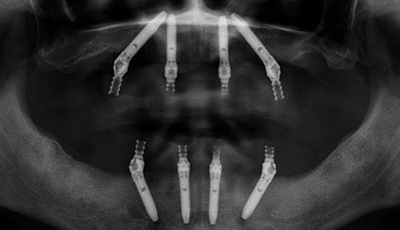

All on 4 refers to a full arch restoration supported by four implants. All on X is a broader term that allows for a customized number of implants based on bone quality, bite forces, and restorative goals.

Your surgical appointment is when dental implants are placed using digitally planned surgical guides. Precision planning allows us to position implants prosthetically, supporting the final smile design from the start.

Once it's been determined that you're a candidate for All-on-4, treatment planning begins using advanced 3D diagnostics to determine precise implant placement. On the day of surgery, any remaining teeth are removed, four implants are placed, and a sturdy set of temporary teeth is attached. After healing and integration with the bone, a custom permanent restoration is placed.